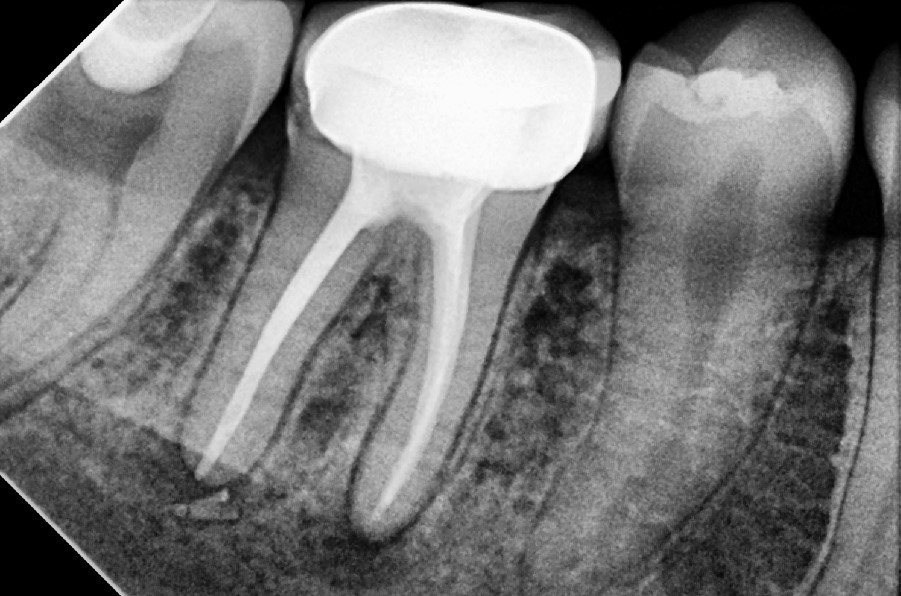

4. Filling the Canals

The clean canals are filled with a biocompatible material called gutta-percha, and sealed to prevent reinfection.

5. Restoration

The tooth is then sealed with a temporary or permanent filling. In most cases, a crown is recommended afterward to strengthen and protect the treated tooth, especially in the back of the mouth.